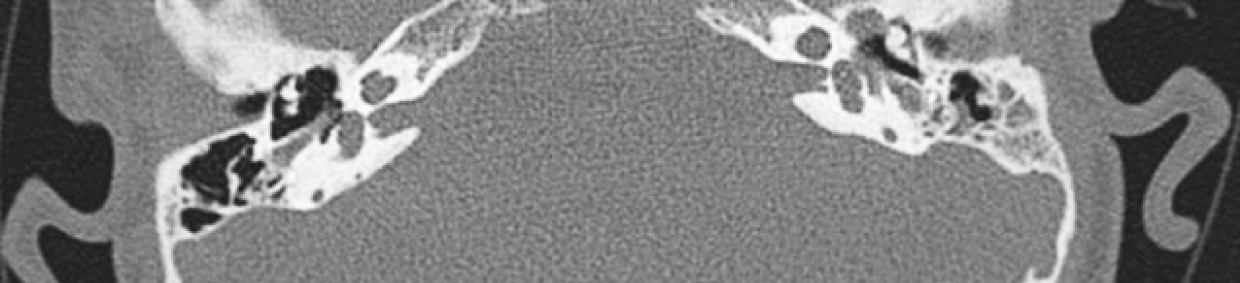

Синдром Кабуки — редкое наследственное заболевание, которое имеет специфическую клиническую картину: характерные черты лица, задержка роста, мышечная гипотония, аномалии скелета, дерматоглифические аномалии, умственная отсталость от легкой до умеренной степени и постнатальный дефицит роста. Синдром Кабуки (синдром маски Кабуки / синдром грима Кабуки) свое название получил за специфические особенности внешнего вида больных, имеющих выражение лица, сходное со специальным гримом, выделяющим глаза и брови персонажей японского театра Кабуки. Основными причинами развития данного заболевания в 75 % являются мутации гена KMT2D (синдром Кабуки 1-го типа) и в 5 % — мутации гена KDM6A (2-го типа), этиология около 20 % случаев остается неизвестной. Большинство мутаций при 1-м типе формируется de novo, также описаны случаи аутосомно-доминантного типа наследования. Синдром Кабуки 2-го типа имеет сцепленное с полом (Х-сцепленное) наследование. Поскольку синдром является мультисистемным заболеванием с низкой распространенностью, пациентам необходимы различные диагностические и скрининговые тесты с междисциплинарной оценкой результатов на разных этапах их жизни. Ранняя диагностика заболевания имеет решающее значение для своевременных лечебно-реабилитационных мероприятий и улучшения прогноза и качества жизни ребенка. Интерес представляемого клинического наблюдения синдрома Кабуки состоит в значимости раннего распознавания клинических проявлений, своевременном оперативном лечении, слухореабилитации и улучшении прогноза жизни пациента. В статье приведено описание клинического наблюдения, генетически подтвержденного синдрома Кабуки 1-го типа, у ребенка 2015 г. р. (тип наследования не установлен). Интерес представляемого клинического наблюдения, проявляющегося характерными чертами лица, аномалиями скелета, постнатальной задержкой роста, дерматоглифическими аномалиями, задержкой интеллектуального развития, состоит в необходимости мультидисциплинарного подхода к диагностике и лечению пациента.